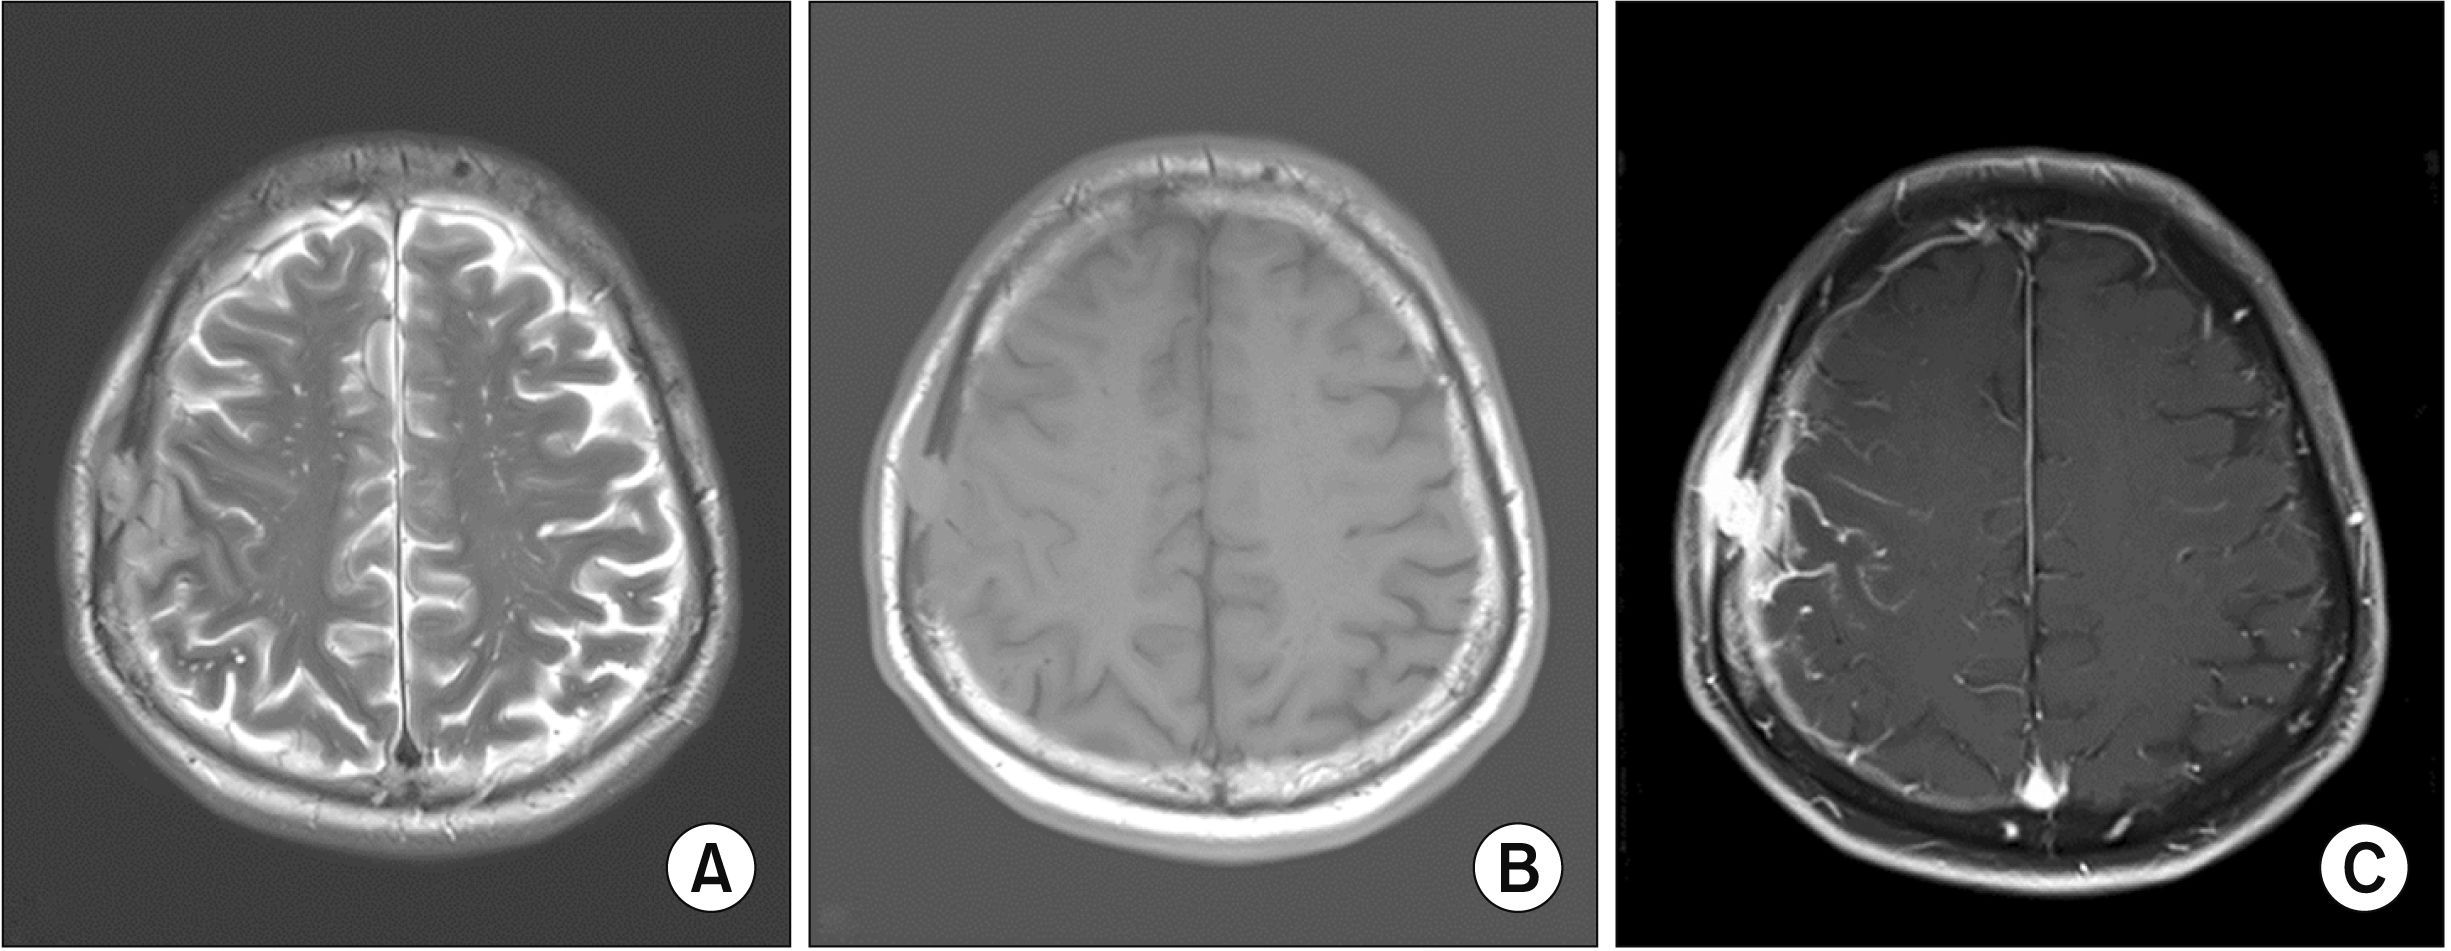

A 63-year-old previously healthy male presented to our neurosurgery department with a palpable mass on the right frontal scalp. He had recognized a palpable mass 1 month previously, accompanied by mild dizziness. There was no history of fever, weight loss, headache, loss of consciousness, or any other neurological and musculoskeletal manifestations. There was no palpable cervical lymphadenopathy, and neurological examination findings were normal. Brain magnetic resonance imaging was performed, which revealed a 1.5-cm enhancing mass with adjacent subgaleal tissue thickening/enhancement and bony destruction in the right frontal area. Dural thickening with enhancement and leptomeningeal enhancement along the right cerebral convexity are shown (Figure 1). Differential diagnosis was recommended for malignant bone tumors or bone metastases combined with pachymeningeal and leptomeningeal metastases. Surgery was performed to diagnose and resect the brain mass. Initial laboratory evaluation revealed an white blood cell count of 7.9×103/μL (reference range: 3.8~10.0×103/μL) with a differential of 69.3% neutrophils (50.0%~75.0%) and 1.5% eosinophil (0.0%~5.0%), hemoglobin of 14.4 g/dL (13.0~17.0 g/dL), and a platelet of 334×103/μL (150~400×103/μL). Routine chemistry, and electrolyte reveled no abnormality. Qauntiferon and serology for hepatitis B and human immunodeficiency virus were negative. Erythrocyte sedimentation rate (ESR) and C-reactive protein (CRP) levels were 25 mm/h (0~10 mm/h) and 2.3 mg/dL (0~0.5 mg/dL), respectively, before the operation; these values decreased to 12 mm/h and 1.51 mg/dL, respectively, on postoperative day one (POD 1). Postoperative histopathology revealed HP with storiform fibrosis, destruction of the skull, and marked infiltrations of lymphocytes, plasma cells, and histiocytes without granulomatous inflammation (Figure 2A and 2B). Immunohistochemistry showed that IgG4-positive cells increased to 68 in a high power field (HPF) with IgG4/IgG ratio of 22.7%, while negative for epithelial membrane antigen and pan-cytokeratin with nonspecific for vimentin was noted (Figure 2C). Although naproxen and antibiotics were administered after the surgery, ESR and CRP increased to 21 mm/h and 3.99 mg/dL, respectively, on the day of consultation (POD 19; Figure 3). The patient was transferred to the rheumatology department for further follow-up and management. For several years, the patient had dry eyes and hearing difficulties in both ears. Tests for antinuclear antibody, antineutrophil cytoplasmic antibody, rheumatoid factor, anti-cyclic citrullinated peptide antibody, and angiotensin-converting enzyme were negative. Chest and abdominopelvic computed tomography revealed no evidence of lymphadenopathy, splenomegaly, and other primary tumors or other organ involvement. Plasma IgG and IgG4 testing were 1,094.4 mg/dL (reference range: 680~1,620 mg/dL) and 9.6 mg/dL (reference range: 3.9~86.4 mg/dL), respectively, on POD 17. Serum levels of ESR and CRP decreased dramatically just one day after starting prednisolone (0.5 mg/kg), which normalized three days after the steroid therapy (Figure 3). The oral prednisolone was slowly tapered off and overlapped with azathioprine (50 mg/day) as maintenance therapy. No evidence of recurrence was found at his two-year follow-up.

Figure 1

Brain magnetic resonance imaging of preoperation shows an enhanced extraaxial mass-like lesion with adjacent subgaleal tissue thickening/enhancement, bony destruction in the right frontal area, dural thickening/enhancement, and leptomeningeal enhancement along the right cerebral convexity. (A) T2-axial, (B) precontrast T1-axial, and (C) postcontrast T1-axial images.